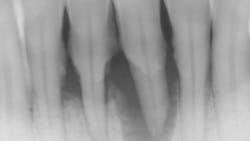

- Ensure tooth does not have a root fracture and check/refer for endodontic treatment if tooth is nonvital (figure 1)